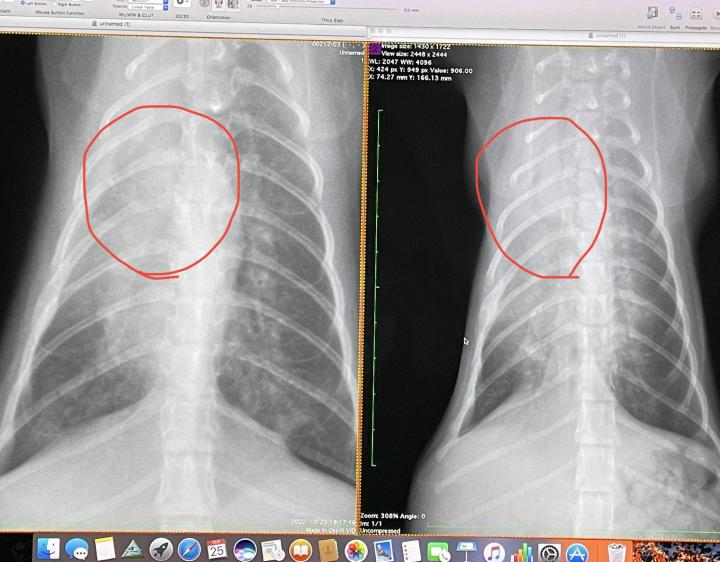

右退院時

左火曜日

赤マルの左肺へ伸びる管がボヤけている

=周辺の肺胞組織が機能し始めた

ということだそうです

つまり

回復傾向である‼️

ということ